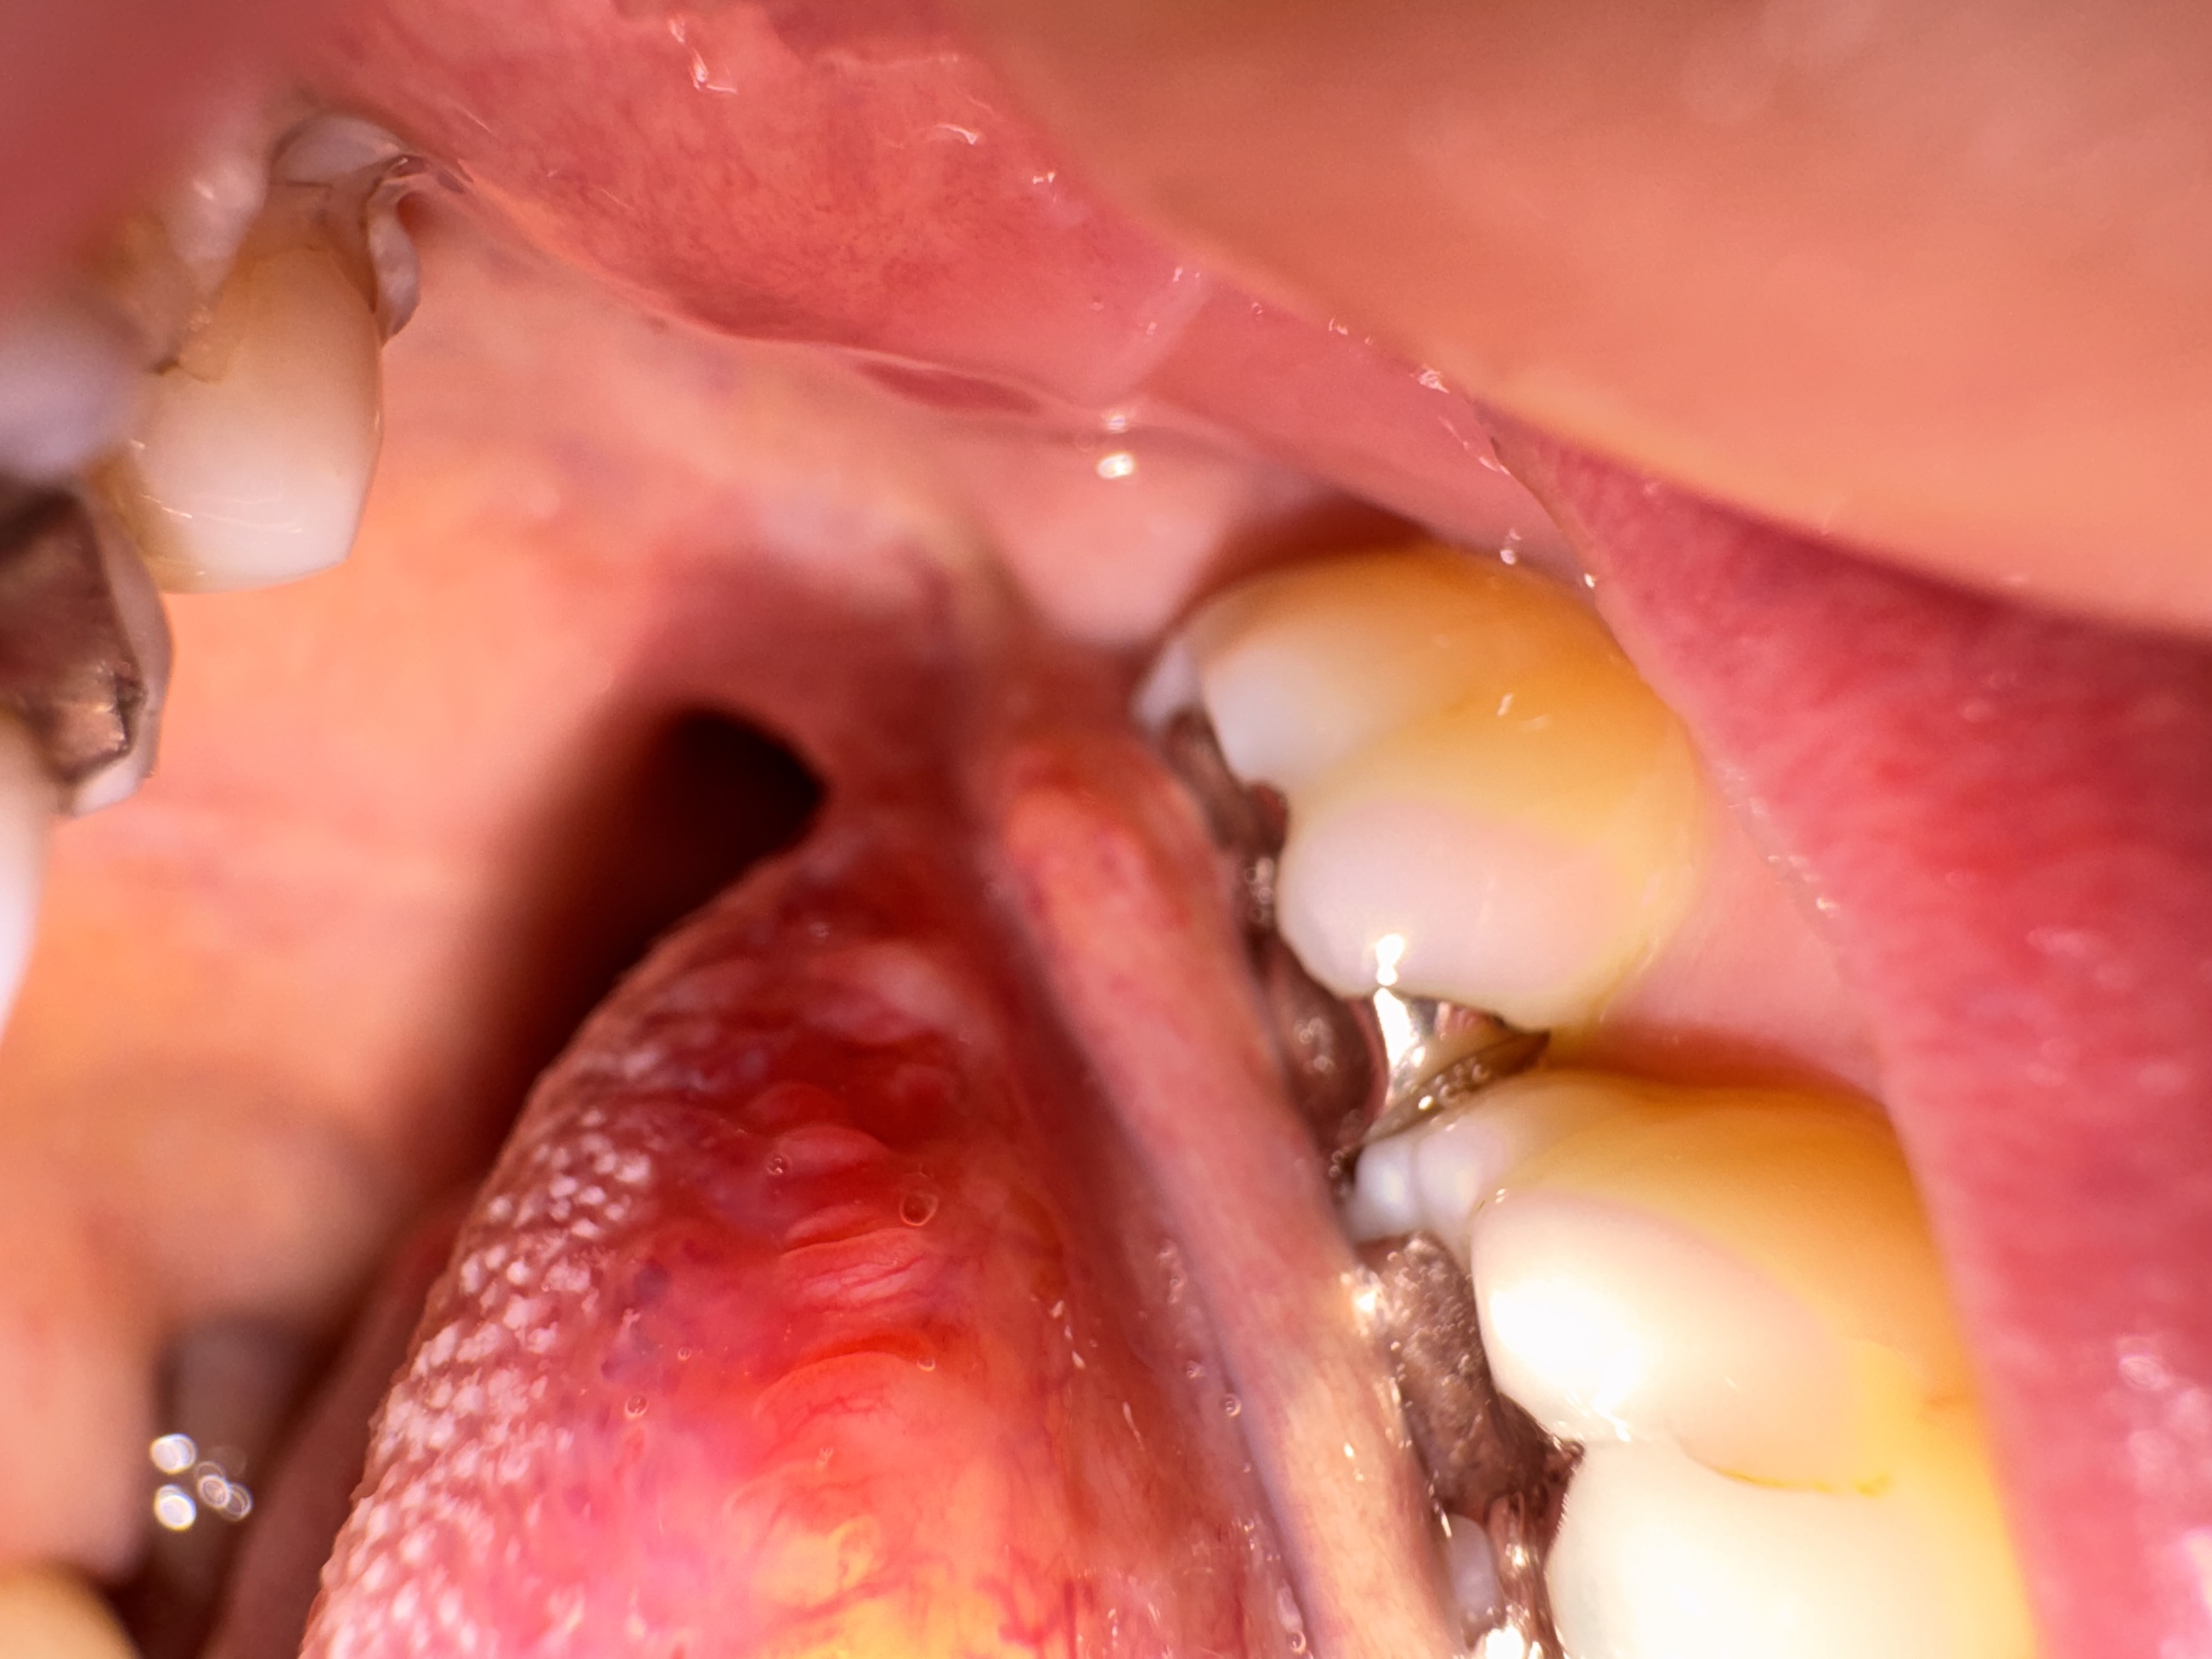

頬の粘膜に口内炎が潰れたような見た目のできものがあります。